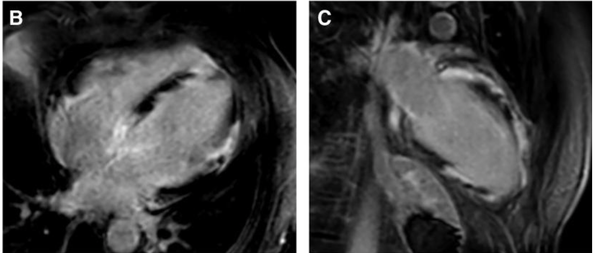

Infiltrative Cardiomyopathy

Granulomatous Cardiomyopathy